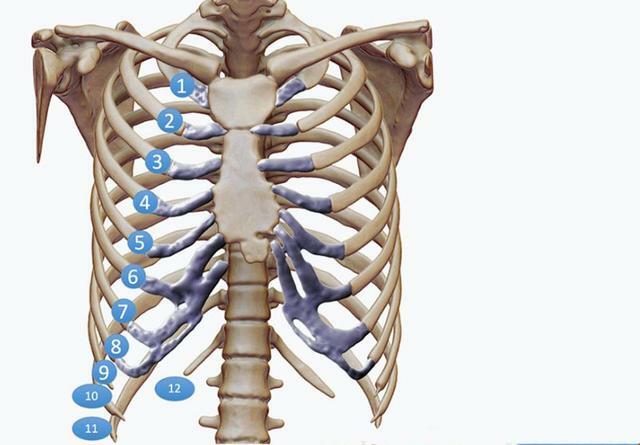

肋骨骨折比較常見,患者中也存在著一些誤解,有些人認為肋骨自己就能長好,另一些則認為非常嚴重,還有的聽說男性天生比女性少一根肋骨,這些觀點都是不準確或者錯誤的,男女的肋骨數量相同,都是12對,受傷後,可能會導致受傷部位立即疼痛、腫脹,淤青,呼吸困難。當深呼吸或進行某些動作(尤其是扭轉)時,胸部疼痛加重。打噴嚏或大笑也會加重。然而這些只是典型症狀,具體到每位患者都有些區別,臨床中肋骨損傷的差別很大,從伴有疼痛和淤青到髮際線輕微骨折,到嚴重的多處肋骨骨折並有移位,各種情況都要考慮到。

由此可見,CT掃描檢查是診斷肋骨骨折的最佳手段。有些骨折X光不一定能看得清。肋骨骨折可由輕微的碰撞引起,也可由嚴重的車禍造成,最容易發生骨折的在第4-7肋骨,不僅因為它們長而且細,並且缺乏上方1-3肋骨的鎖骨和肩胛骨的保護。往下則是第10-12肋骨,它們的一端是懸空的,不固定在任何骨頭上,彈性大,也不容易骨折。